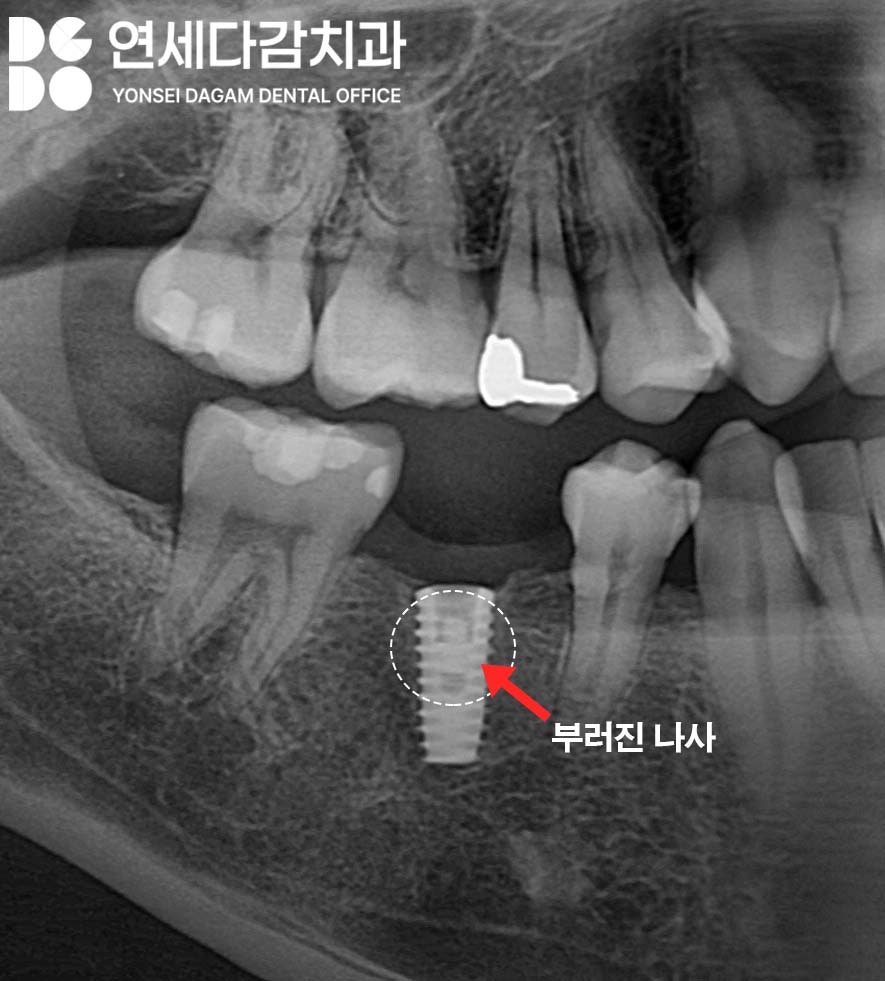

부러진 나사 조각이 있다면

꺼내면 되는 거 아닌가?

라고 단순하게 생각할 수 있지만

부러진 나사 부분이 fixture 내부에

단단히 체결되어 있을 경우

복잡한 상황이 되어버립니다.

이럴 땐 임플란트 재수술을

권하는 경우도 있을 정도로

빼는 게 불가능한 상황일 때도 있죠.

부러진 보철 나사를 제거하는

방법은 크게 두 가지가 있습니다.

첫 번째는 임플란트 회사에서

제공하는 전용 제거 키트를

사용하는 방법입니다.

이 키트를 이용하면

fixture 내부에 약간의 손상이

생길 수는 있으나,

재수술보다는 환자의 부담이

훨씬 적습니다.

두 번째는 보철 나사와

픽스처 나사선 사이에

미세한 진동을 지속적으로 주어

나사를 풀어내는 방법입니다.

일반적으로 치석 제거할 때

사용하는 스케일러를 활용하여

진동을 전달하게 됩니다.